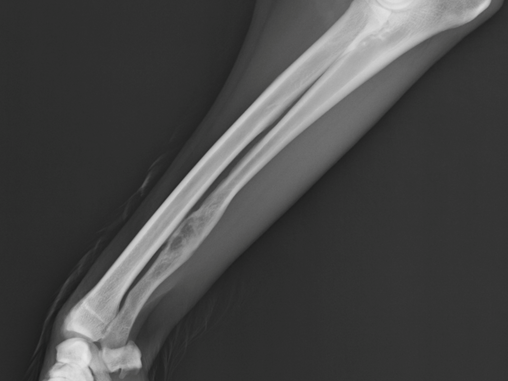

Benign ulna lesion